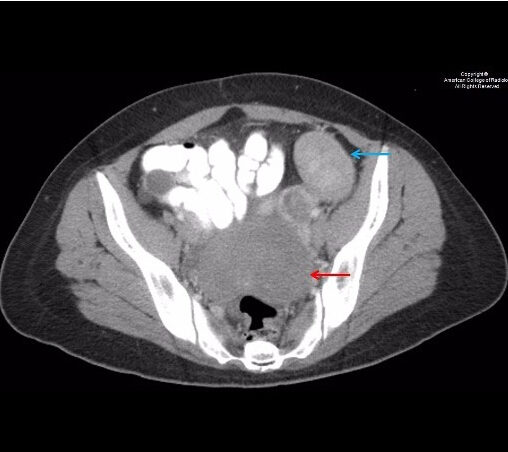

基本病史:患者女性,40 岁,腹痛,几年前曾做过子宫切除术。行腹部 CT 和 MR 检查,结果如下。![]() ![]() ![]() ![]() ![]() ![]() ![]() 诊断:弥漫性腹膜平滑肌瘤病 病例要点 弥漫性腹膜平滑肌瘤病是一种罕见的良性肿瘤,好发于育龄期女性,术前常误诊为子宫肌瘤,疾病受激素影响。 弥漫性腹膜平滑肌瘤在影像学上的特点,主要表现为腹膜或盆腔的小结节或大的实性软组织团块。鉴别诊断主要包括:腹膜转移癌,淋巴瘤,结核性腹膜炎,原发性腹膜间皮瘤,硬纤维瘤和平滑肌肉瘤。 MRI 可通过均匀对比度增强,显示与骨骼肌和平滑肌相似的信号强度,进而协助该病的诊断。 讨论 在腹膜上生长的众多平滑肌肿瘤中,弥漫性腹膜平滑肌溜病是其中一种罕见的良性肿瘤。好发于育龄期女性,其中又有很大一部分人合并子宫肌瘤切除术或子宫切除术。其他危险因素包括激素的影响,如妊娠,长期口服避孕药和卵巢颗粒细胞瘤。 腹膜转移癌是最令人重视的鉴别诊断。然而,转移癌的病人通常会体重下降和有腹水。肿瘤可以表现为浸润生长或是多发小结节,但是大的孤立性实性团块不常见。弥漫性腹膜平滑肌瘤病可以于无症状病人偶然发现,结节可大可小。全身症状不明显。原发性腹膜间皮瘤更常见于男性,常表现为腹膜内浸润的斑块和团块。 腹膜结核表现为低密度坏死结节灶。淋巴瘤表现为非坏死、非钙化的均质性腹膜后淋巴结肿大,通常不伴有明显的强化。平滑肌肉瘤有不典型增生,同时还有 FDG 摄取,在病理学上是恶性的。无法单独用影像学检查来区分平滑肌瘤为低度恶性还是良性。

MRI 见平滑肌瘤与骨骼肌和平滑肌有相似的 T1/T2 信号强度,并且静脉注射造影剂时同质强化。影像引导的经皮穿刺活检有助于诊断,但确诊需要剖腹探查和(或)组织检查明确病理为良性。治疗包括通过切除或非切除的手段移除所有的外源激素灶。因有罕见的肉瘤变可能,故需随访。 |